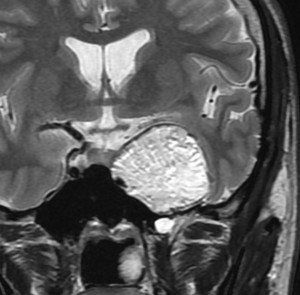

前頭蓋底類皮のう胞

蝶形骨平面から鞍結節上に発生するもので多いタイプです。左側のT2強調画像で内容物がまだらに見え,右側の拡散強調画像で高信号(白い)に見えるので診断確定です。内頸動脈や前大脳動脈や穿通枝などとの癒着が強いものが多いので剥離は難しく要注意です。ある程度の大きさを超えると経鼻内視鏡手術では摘出できません。この腫瘍は脳槽内にあるので,一回の手術でのう胞の壁も含めて全部摘出しなければなりません。そうしないと,手術後に内容物(皮脂と汗とケラチン)が髄液の中に産生されて漏れ出て,難治性の水頭症になります。